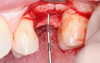

Emergence Transition

The emergence transition of the abutment transition is an obvious necessity following the base-level abutment transition to the tissue level (Figure 2). If the base abutment is at 25°, then the emergence transition must occur to have a transition to the zenith on the buccal and lingual soft tissue. The desired wineglass shape of the transition from the vertical component of the base abutment creates an attachment of the junctional epithelium. Interproximal contact points are also crucial in maintaining and promoting papilla formation. It is usually necessary to place an "anatomic healing abutment" or an immediate temporary to establish both esthetics and the protective vertical soft tissue needed for maintaining crestal bone.

Fig 2. Emergence transition with implant platform depth of 4 mm from zenith.

Figure 2